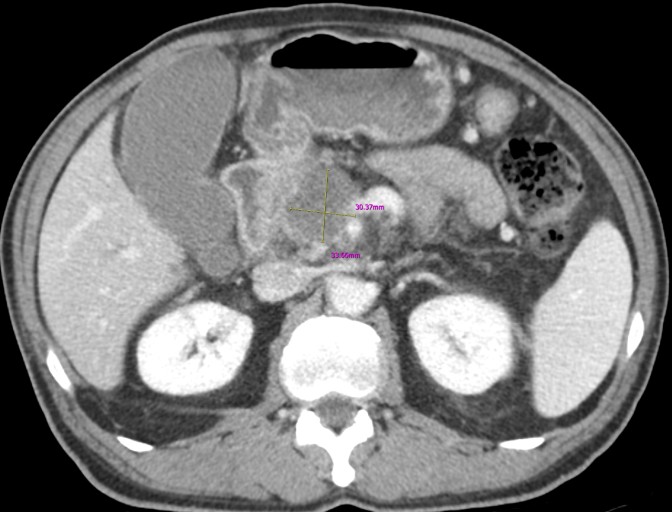

오늘은 가장 치명적인 암 중 하나로 알려진 췌장암의 초기 증상에 대해 이야기하려 합니다. 췌장암은 췌장(이자)에 발생하는 암으로, 췌장이 몸 깊숙한 곳에 위치하고 있어 초기 증상이 모호하거나 다른 소화기 질환과 비슷해 진단이 매우 어렵습니다.

췌장암은 종양의 위치나 크기에 따라 증상이 매우 다양하게 나타납니다. 초기에는 자각 증상이 거의 없어 병이 상당히 진행된 후에 발견되는 경우가 많으므로, 아래 증상들이 복합적으로 나타난다면 즉시 정밀 검사를 받아봐야 합니다. 다음은 췌장암 환자들이 흔히 겪는 10가지 주요 초기 증상입니다.

- 복합적인 증상 주의: 단순 소화 불량이 아닌, 복부 통증 + 체중 감소 + 황달 + 새로운 당뇨병 등 여러 증상이 복합적으로 나타나면 즉시 병원을 찾아 정밀 검사(복부 CT, MRI, 내시경 초음파 등)를 받아야 합니다.